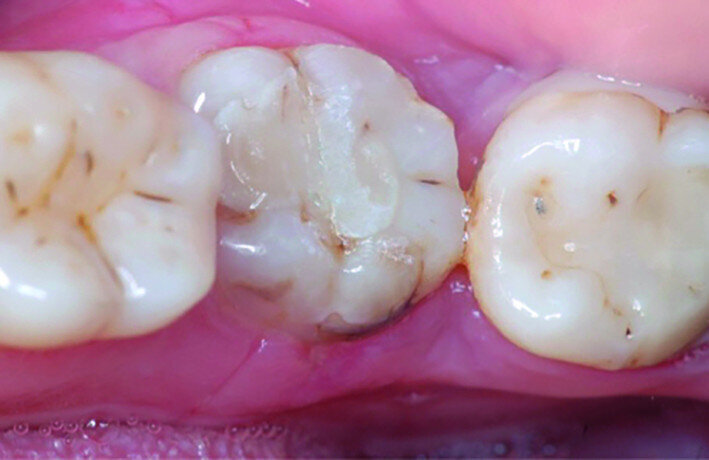

Fig. 1: Pre-op occlusal view.

Fig. 2: Pre-op facial view.

A 47-year-old male patient in a good medical condition and a non-smoker was referred to our dental practice for endodontic retreatment of the right maxillary second molar. The dental history revealed that the tooth had been endodontically treated three months before because of acute pulpitis. After the treatment, the patient complained of pain on chewing. Antibiotics and a non-steroidal anti-inflammatory drug were prescribed, but the pain remained. After a month, a sinus tract appeared. The tooth was retreated in another practice without success. The clinical inspection revealed the presence of a sinus tract near the apical region of tooth #17. The tooth had been prepared for a full crown, but was without even a temporary crown, and the access cavity had been closed with temporary filling material. Cracks were evident on the buccal and mesial surfaces. Periodontal probing showed a deep pocket (> 12 mm) on the distal aspect of the root trunk (Figs. 1 & 2). The periapical radiograph showed a radiolucency between the roots of the second and third molars. The radiographic appearance of the endodontic treatment was good, without clear evidence of periapical radiolucencies (Fig. 3). A perforation of the pulp chamber floor was suspected. A CBCT scan was performed (Figs. 4–7), and it confirmed the suspicion of perforation, along with the presence of a large periradicular radiolucency and an unfavourable root shape.